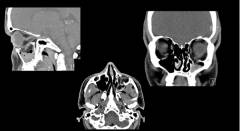

При воспалении лобных, верхнечелюстных или клиновидных пазух (синусит) необходима консультация ЛОР-врача. Диагностика фронтита, гайморита или этмоидита обычно несложна: сбор анамнеза и клиническое обследование (осмотр носовой полости, пальпация пазух) позволяют определить природу заболевания. Для точного диагноза чаще всего используют рентгенографию околоносовых синусов в одной или двух проекциях. Затемненные участки в пазухах указывают на наличие патологического содержимого (гноя). В некоторых случаях применяются компьютерная томография или магнитно-резонансная томография, но их результаты не сильно отличаются от рентгенографии и стоят дороже.